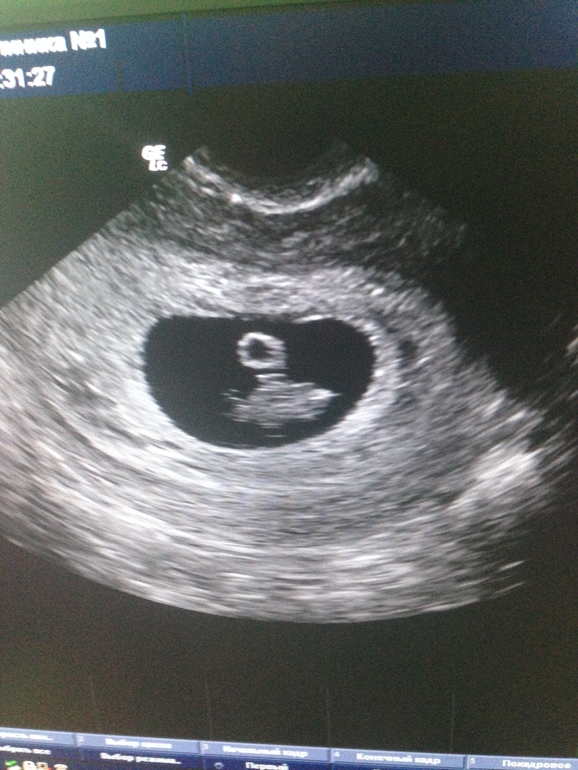

И вот появились рожки,

Не рожки это, а ножки!

А вот две закорючки.

Ну что вы, это же ручки!

Смотрите: носик, брови, веки.....

Вот так образуются человеки!!!

Нашему чуду, уже 14 недель, время так быстротечно, что я со всеми тревогами и переживаниями не могу насладиться своим чудесным положением.....

Животик ещё не показался, но бугорочек чуть выше лобка, я ни с чем не перепутаю)

Малыш я уже люблю тебя, и не представляю жизни без тебя.....